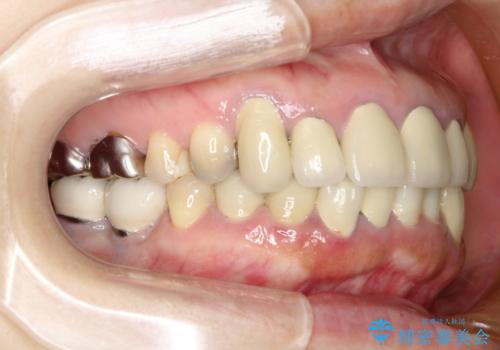

- 下顎の前歯に激痛を覚えて来院された患者様です。

取り急ぎ下顎前歯数歯の根管治療を、銀座しらゆり歯科医院長の林先生にお願いし、それ以外に気になっている、不自然な色調のクラウン、金属部分が見えてブラッシングがしにくいインプラント補綴、口元の突出感、出血のしやすい歯周ポケットなど、全てを解決するための治療を行うこととしました。

期間と費用はかかりましたが、気になっていた部分全てを改善でき、患者様には大変満足していただきました。